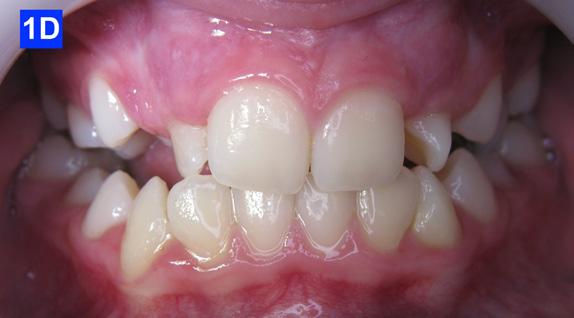

Clinical Micro-esthetic appraisal revealed Angle Class I molar relationship. The arches were narrow, there was crowding, and she had a posterior crossbite. The patient had 2.0 mm overjet and 1.5 mm overbite. There was an anterior cross bite on #12(7) and #22(10), which indicates Class III tendency. The lower airway was very narrow, only 5.0 mm; however, the patient denied SDB symptoms. She did, however, present with symptoms and signs of TMJ dysfunction (Figure 1-D, E, F, G, H,)

Figure 1D: Pre-treatment, frontal view

Figure 1E: Pre-treatment, right lateral view

Figure 1F: Pre-treatmrnt, left lateral view